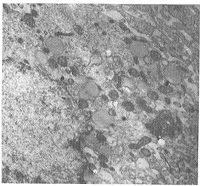

2.2 人肺癌细胞胞质骨架的形态结构(图1~4) 在透射电镜下,肺癌细胞核畸形,核仁肥大,多呈致密型或网状,可见双核、多核。与PG细胞相比,PAa细胞中微管、微丝稀疏但可见,而PG细胞中微管、微丝则明显减缺;PG细胞比PAa细胞核仁更多,分裂相多见,细胞膜微绒毛较多。经VCR处理后,两种细胞均有脂滴增加,微管减少,内质网扩张,空泡形成,甚至出现细胞蜕变、胞膜缺损等改变,PG细胞呈现分裂期形态表现较为多见。

图1 未经VCR处理的PAa细胞,可见稀少的微管、微丝 ×17000

Fig 1 The microtubules and microfilaments were sparse random in the PAa cells untreated with VCR. ×17000